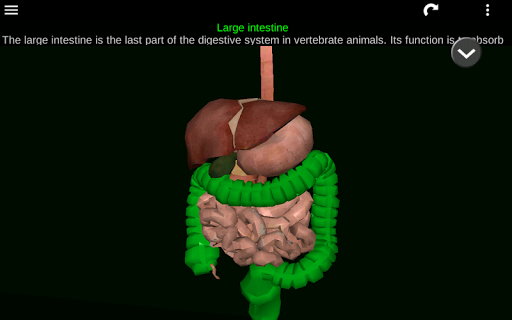

* Sistem pencernaan, termasuk lambung, usus kecil, usus besar, dan animasi sistem ini.